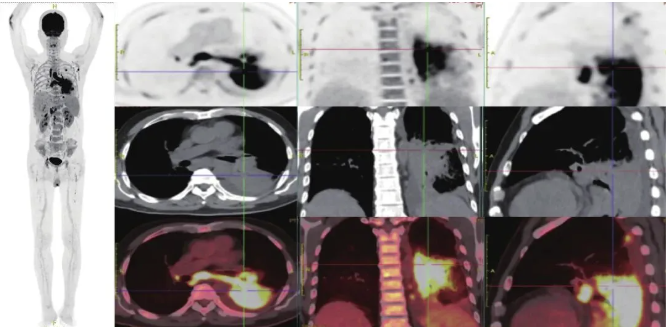

18F-FDG全身PET/CT显像(图2):(1)左下肺实变伴代谢弥漫性增高,余双肺多发结节及条片状磨玻璃密度影,代谢轻度增高,结合患者病史及实验室检查,考虑为感染性病变。(2)左侧腋窝、左锁骨下、双侧肺门、纵隔、左侧内乳区、肝胃间隙、脾胃间隙、胰头周围、腹主动脉两旁、右侧髂血管旁、右侧腹股沟区多发高代谢淋巴结,考虑为淋巴结炎性增生。(3)右下胸膜单发高代谢结节,肝脏多发高代谢结节,脾脏单发高代谢结节;肝脾饱满,脾脏代谢弥漫增高;胸5左侧附件高代谢结节,全身骨髓代谢弥漫增高,综合考虑为感染性病变。

图2 18F-FDG全身PET/CT像

复查PET-CT:(1)原左下肺实变代谢弥漫性增高灶,体积较前增大,代谢增高(图1d),余双肺多发结节较前明显缩小、数量较前减少,代谢基本降低至本底水平,综上考虑为TM感染治疗后活性较前好转;(2)原左侧腋窝、左锁骨下、双侧肺门、纵隔、左侧内乳区、肝胃间隙、脾胃间隙、胰头周围、腹主动脉两旁、右侧髂血管旁,右侧腹股沟区多发高代谢淋巴结,体积较前缩小,部分较前消失,代谢较前减低,考虑为TM感染治疗后活性部分受抑,但仍有活性残余;(3)右后下胸膜单发高代谢结节体积较前缩小,代谢较前明显减低原肝脏、脾脏及胸5左侧附件多发高代谢结节较前消失,综上所述考虑为TM感染治疗后活性基本受抑。